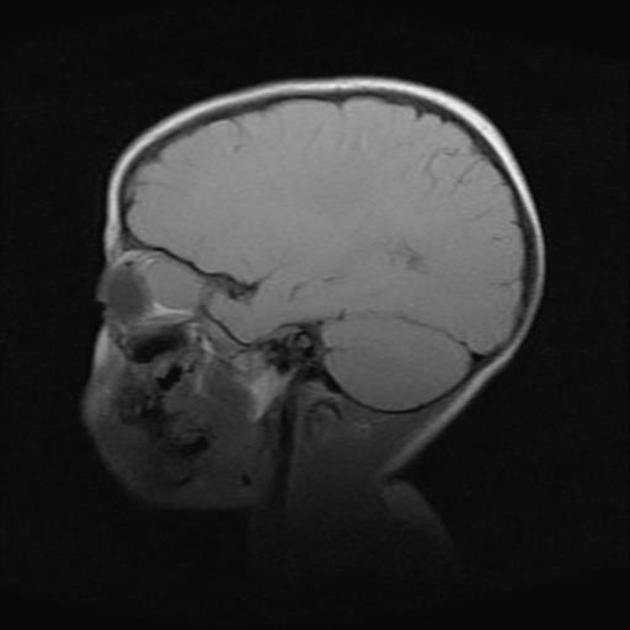

案例四

基本病史:11 岁女孩,神经纤维瘤病(I 型)患者。

图 4 MRI 检查 T2WI 和 T1WI 强化序列显示,双侧视神经视交叉附近呈明显肿胀,长 T2 异常信号,增强呈明显强化改变